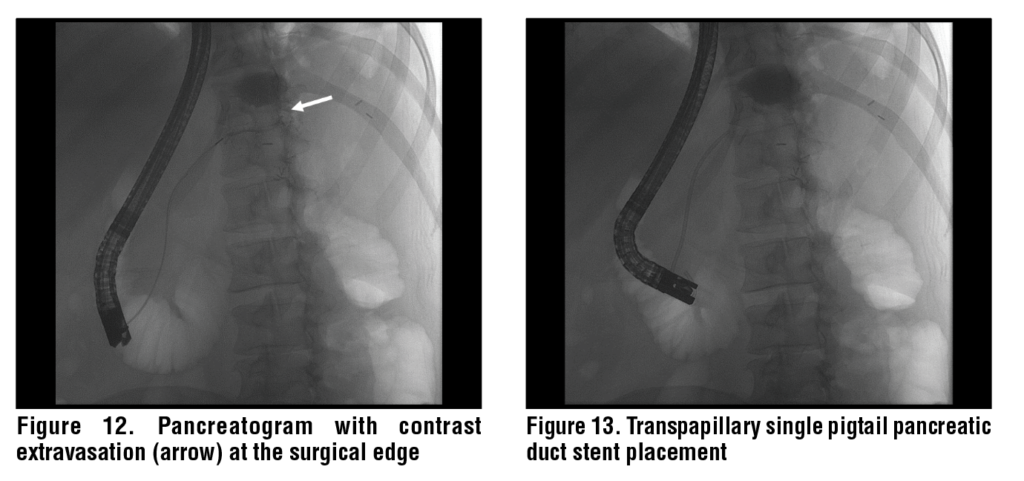

Transpapillary drainage involves an ERCP with insertion of a PD stent that bridges the site of PD disruption. (See Figures 11-13.) Bridging the site of PD disruption with a PD stent promotes physiological flow of pancreatic fluid into the duodenum rather than through the site of PD disruption and correlates with successful outcomes.24,25 Additionally, PD stents can be used to bypass areas of ductal obstruction due to PD stones and strictures. The stent diameter depends on the PD diameter and should not exceed the diameter of the upstream PD.26 While pancreatic sphincterotomy is not required for stent insertion, it can be used to facilitate stone extraction and PD stricture dilation and is often performed if the need for repeated PD access is anticipated in the future. Optimal stent duration/indwell time is unclear and depends on the etiology of the PD leak and operator preference. In cases where the upstream portion of the PD is unable to be accessed, a shorter stent can be placed, with a plan to re-attempt ERCP to bridge the leak at a later date. In most case series, PD stents were left in place for 4-8 weeks with shorter durations being associated with an increased risk of recurrence or failure and longer durations being associated with stent occlusion and ductal changes in a previously otherwise normal PDs, but this has not been universally reported.24,25,27–29 Importantly, many patients need, and tolerate, long PD stent indwell times without any evidence of duct injury. Lastly, transpapillary drainage can be used to drain PFCs that communicate directly with the main PD. This technique involves placing the distal aspect of the stent directly into the PFC and is supported by case-series that have demonstrated its effectiveness, though it is not the preferred route of drainage.30,31 (See Figure 14.) Even if the PD does not clearly communicate with the PFC, a PD stent can still help to prevent backfilling of the PFC and can promote resolution.